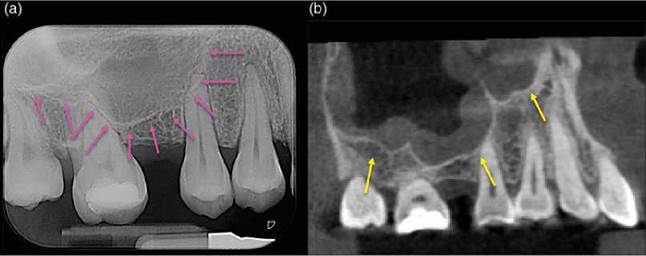

Conventional radiography: The periodontal ligament space is the soft tissue connecting the dental cementum and the lamina dura of the surrounding bone. The fact that the periodontal ligament is radiolucent and that the bordering structures of the periodontal ligament space are mineralized and relatively radio-dense means that the periodontal ligament space is represented radiographically as a thin, well-defined radiolucency sur- rounding the root of the tooth. The periodontal ligament effectively supports the tooth within the alveolar bone and permits physiological mobility. The width of the periodontal ligament space may increase with increased tooth mobility as might occur in advanced marginal periodontitis or in traumatic occlusion (Figure 6.5).

CBCT: The appearance of the periodontal ligament space is similar when assessed using conventional radiography and CBCT. However, CBCT allows the periodontal ligament space to be observed in all plains and without interference caused by adjacent anatomical structures (Figures 6.6 and 6.7). Indeed there is in vitro and in vivo evidence to suggest that CBCT permits better visibility of both simulated periodontal ligament and natural periodontal ligament spaces when compared to conventional radiography [58, 98].

Figure 6.5 Periodontal ligament space. (a and b) Periapical radiographs of mandibular posterior teeth. The PDL space and lamina dura associated with tooth 45 can be evaluated in the mesio-distal plane. (c-e) CBCT images of the same tooth in the (c) axial, (d) coronal and (e) sagittal planes permit a more objective appreciation of the PDL space and lamina dura associated with the tooth.

Figure 6.7 Periodontal ligament space. (a) Periapical radiograph of tooth 36 and 37, demonstrating widening of the PDL space on the mesial roots each tooth (yellow arrows). Both had symptoms of irreversible pulpitis. (b) Periapical radiograph of tooth 37, which is a lone standing tooth and the terminal tooth in the arch. Widening of the PDL space on the mesial aspect of the tooth (pink arrows) is related to traumatic occlusion.